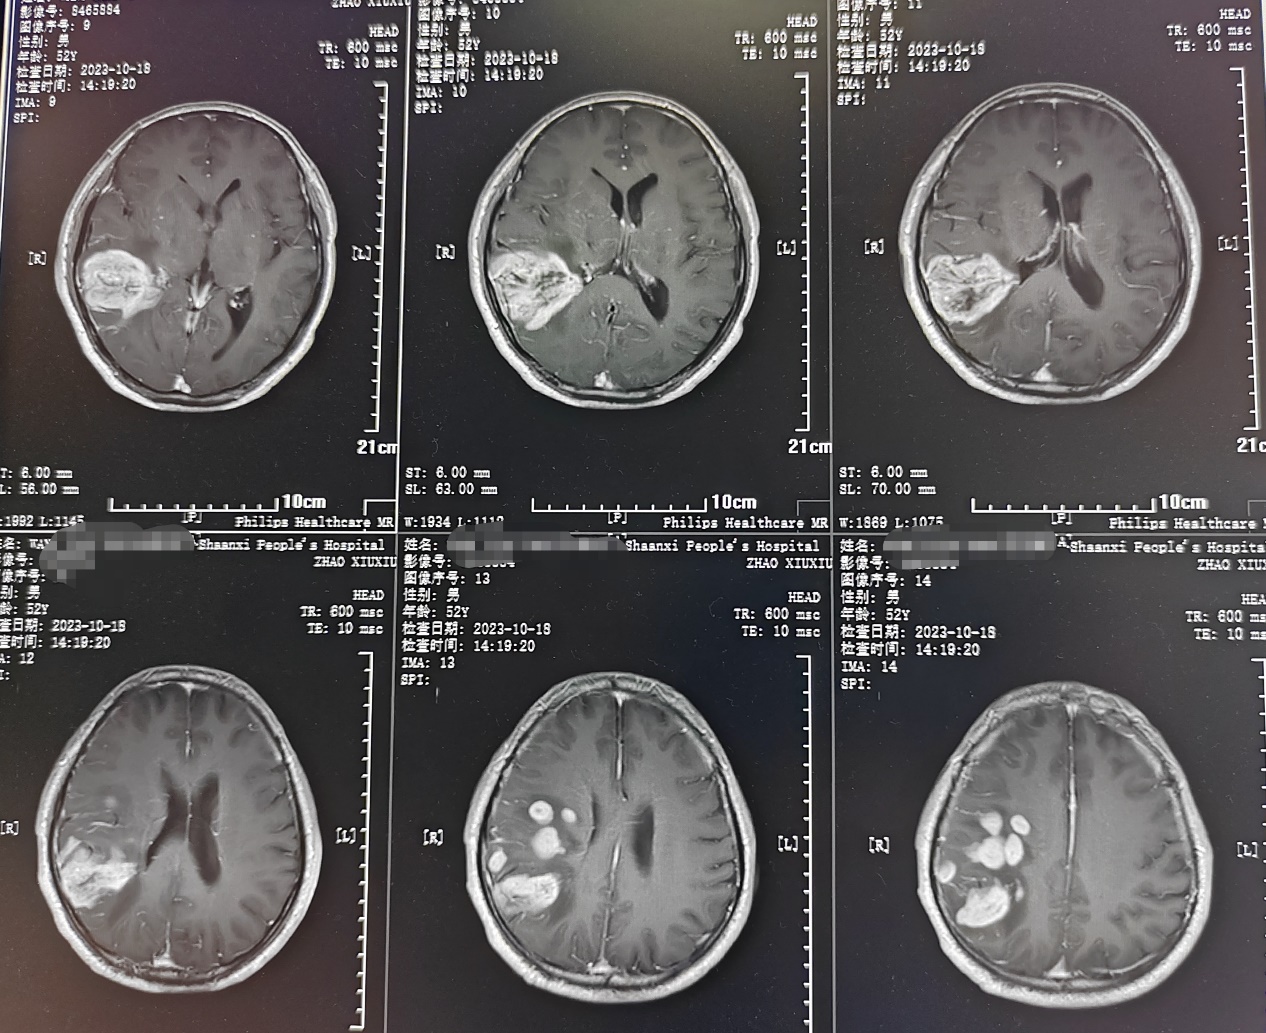

患者为成年男性,因头痛伴间断晕厥1月,在当地黑料网

检查发现右颞顶叶多发占位病变,考虑胶质瘤。因肿瘤功能区关系密切,术后可能出现肢体运动障碍。如何做到在尽量全切肿瘤同时做好神经功能保护,对于神经外科医生来说是一种挑战。术前全科详细讨论病例制定了手术方案,决定在电生理监测下进行手术,近日由缪星宇主任医师、孟发财副主任医师、刘凯飞主治医师成功为患者实施了手术。术中在电生理运动诱发电位的监测下,结合多模态影像技术,显微镜下全切肿瘤,成功利用电生理监测技术保留运动区结构和功能,术后患者恢复顺利,病理结果确定胶质瘤诊断。